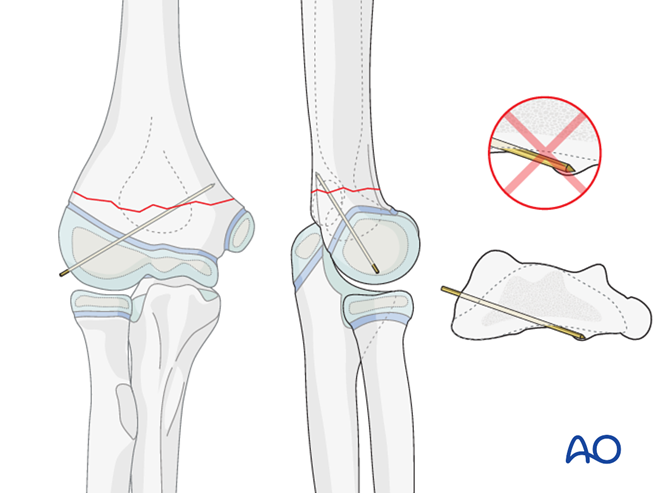

一,儿童骨化中心